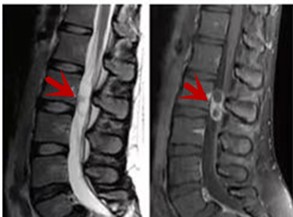

利器三:MRI(核磁共振)

MRI利于磁場(chǎng)和射頻脈沖使體內(nèi)的氫原子核發(fā)生磁共振現(xiàn)象而產(chǎn)生的圖像,對(duì)軟組織的分辨率很高,對(duì)于脊髓、椎間盤、神經(jīng)、血管、韌帶、骨髓、腰部肌肉及周圍軟組織有很好的顯示效果,可以清晰的顯示腰椎間盤突出對(duì)硬膜囊、神經(jīng)根壓迫程度,以及骨折是陳舊還是新鮮,同時(shí)在脊髓病變(如脊髓損傷、髓內(nèi)出血或腫瘤)、椎管內(nèi)膿腫/血腫、椎旁肌肉軟組織病變等方面也具有優(yōu)勢(shì),但是檢查時(shí)間較長(zhǎng),部分患者可能因體內(nèi)金屬植入物(如心臟起搏器、人工耳蝸等)而無法進(jìn)行檢查。

箭頭提示腰椎管內(nèi)腫瘤

紅色箭頭提示新鮮骨折,黃色箭頭提示陳舊性骨折